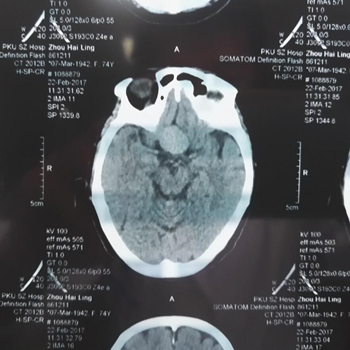

检查结果显示双眼视神经萎缩及视野缺损

于是邢主任给她做了进一步检查,通过OCT与视野计检查结果,邢宝刚主任判断张奶奶视野缺损的情况应该不是单纯的眼睛问题,极有可能是脑内肿瘤引起的。于是邢宝刚主任建议张奶奶去做脑部CT扫描检查。

没想到,这一查,果然脑部长了一个约21*25mm大小的肿瘤,就是它压迫了视神经,导致视野缺损。“脑子里的肿瘤,这个尺寸已经是很大的了。”